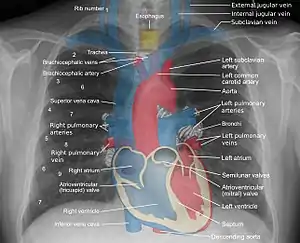

![]() A normal posteroanterior (PA) chest radiograph of someone without any signs of injury. Dx and Sin stand for "right" and "left" respectively. | |

A chest radiograph, called a chest X-ray (CXR), or chest film, is a projection radiograph of the chest used to diagnose conditions affecting the chest, its contents, and nearby structures. Chest radiographs are the most common film taken in medicine.

Chest radiographs are used to diagnose many conditions involving the chest wall, including its bones, and also structures contained within the thoracic cavity including the lungs, heart, and great vessels. Pneumonia and congestive heart failure are very commonly diagnosed by chest radiograph. Chest radiographs are also used to screen for job-related lung disease in industries such as mining where workers are exposed to dust.[3]

Landmarks

In the average person, the diaphragm should be intersected by the 5th to 7th anterior ribs at the mid-clavicular line, and 9 to 10 posterior ribs should be viewable on a normal PA inspiratory film. An increase in the number of viewable ribs implies hyperinflation, as can occur, for example, with obstructive lung disease or foreign body aspiration. A decrease implies hypoventilation, as can occur with restrictive lung disease, pleural effusions or atelectasis. Underexpansion can also cause interstitial markings due to parenchymal crowding, which can mimic the appearance of interstitial lung disease. Enlargement of the right descending pulmonary artery can indirectly reflect changes of pulmonary hypertension, with a size greater than 16 mm abnormal in men and 15 mm in women.[6]

Appropriate penetration of the film can be assessed by faint visualization of the thoracic spines and lung markings behind the heart. The right diaphragm is usually higher than the left, with the liver being situated beneath it in the abdomen. The minor fissure can sometimes be seen on the right as a thin horizontal line at the level of the fifth or sixth rib. Splaying of the carina can also suggest a tumor or process in the middle mediastinum or enlargement of the left atrium, with a normal angle of approximately 60 degrees. The right paratracheal stripe is also important to assess, as it can reflect a process in the posterior mediastinum, in particular the spine or paraspinal soft tissues; normally it should measure 3 mm or less. The left paratracheal stripe is more variable and only seen in 25% of normal patients on posteroanterior views.[7]

Localization of lesions or inflammatory and infectious processes can be difficult to discern on chest radiograph, but can be inferenced by silhouetting and the hilum overlay sign with adjacent structures. If either hemidiaphragm is blurred, for example, this suggests the lesion to be from the corresponding lower lobe. If the right heart border is blurred, than the pathology is likely in the right middle lobe, though a cavum deformity can also blur the right heard border due to indentation of the adjacent sternum. If the left heart border is blurred, this implies a process at the lingula.[8]